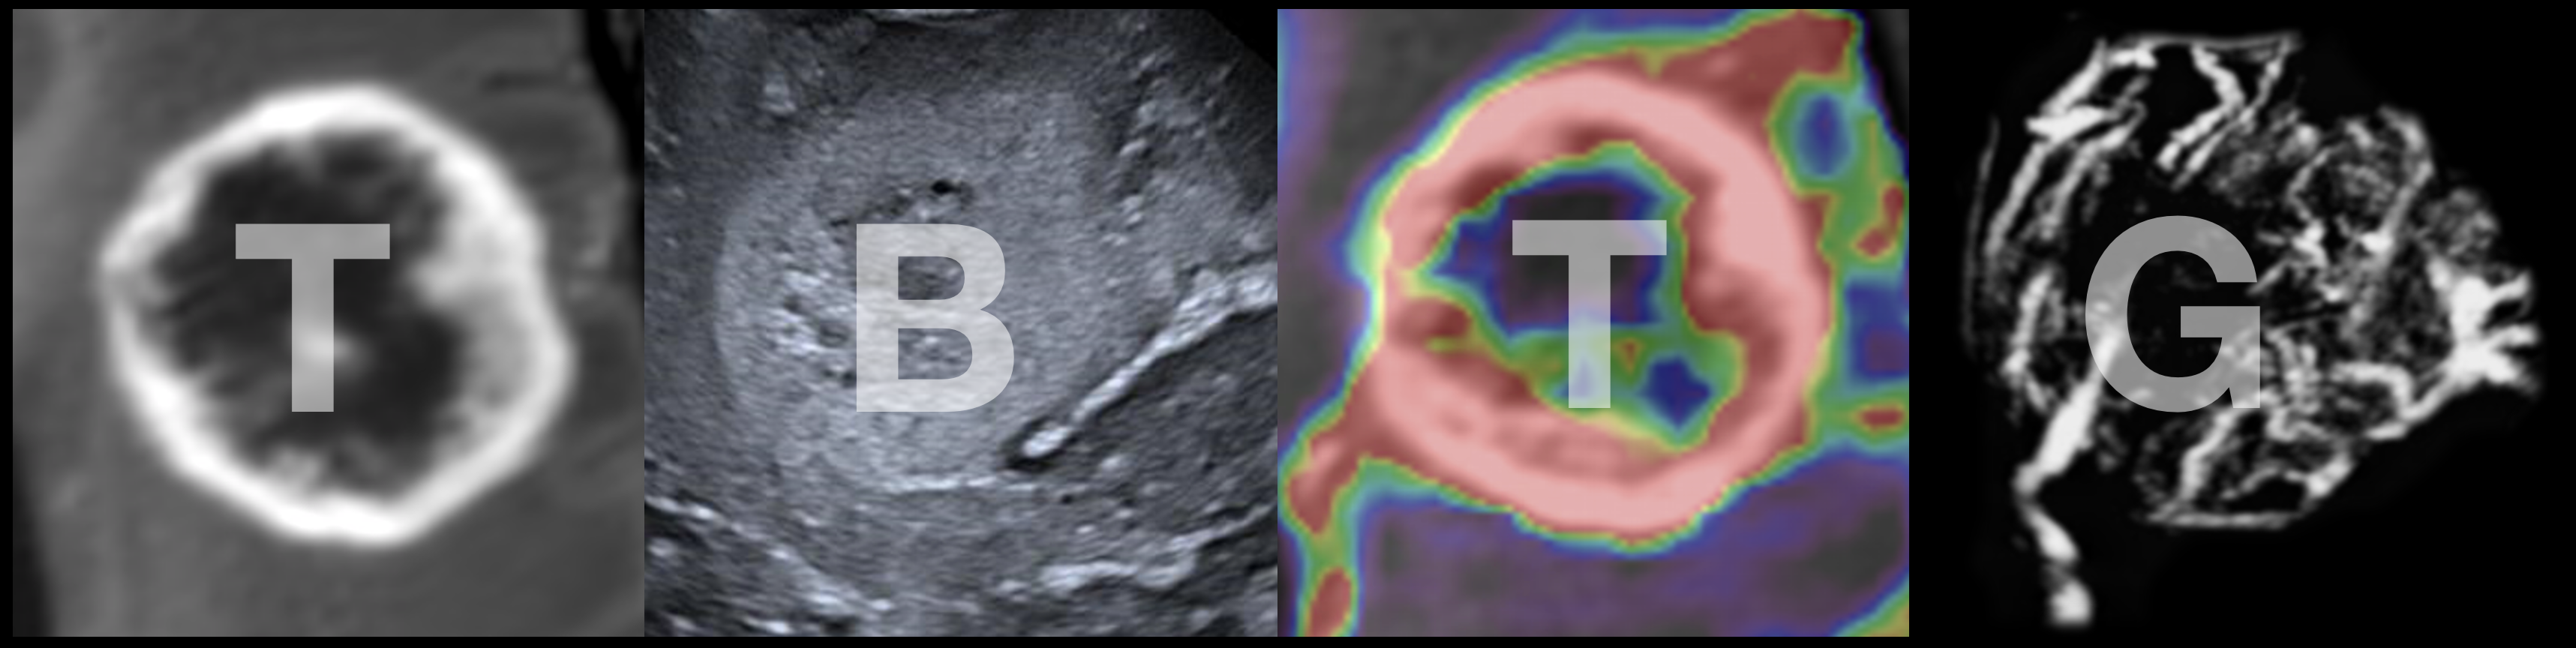

The Translational Brain Tumour Group is a joint clinical and engineering initiative, which spans imaging, neurosurgery and oncology led by Sophie Camp (Neurosurgery), Matthew Grech-Sollars (Imaging), Luke Dixon (Neuroradiology) and Matt Williams (Neuro-Oncology), based in the Department of Surgery and Cancer at Imperial College London.

Brain tumours are the leading cause of cancer death in the under-40’s, and survival rates have not improved in the last 10 years. Treatment is complex, and involves a combination of surgery, radiotherapy and chemotherapy, and relies heavily on imaging to diagnose patients, plan treatment and assess response. Our research is focused on multi-modality approaches to improving outcomes for brain tumour patients, and aims to integrate developments in surgery, oncology and imaging. Our work covers both primary and secondary brain tumours (metastases), and we are particularly interested in how we can combine better imaging with combinations of treatments to improve outcomes.

We are exploring better techniques to assess and measure responses to brain tumours, using a variety of approaches including ultrasound and MRI, and improving their interpretation using computational methods.